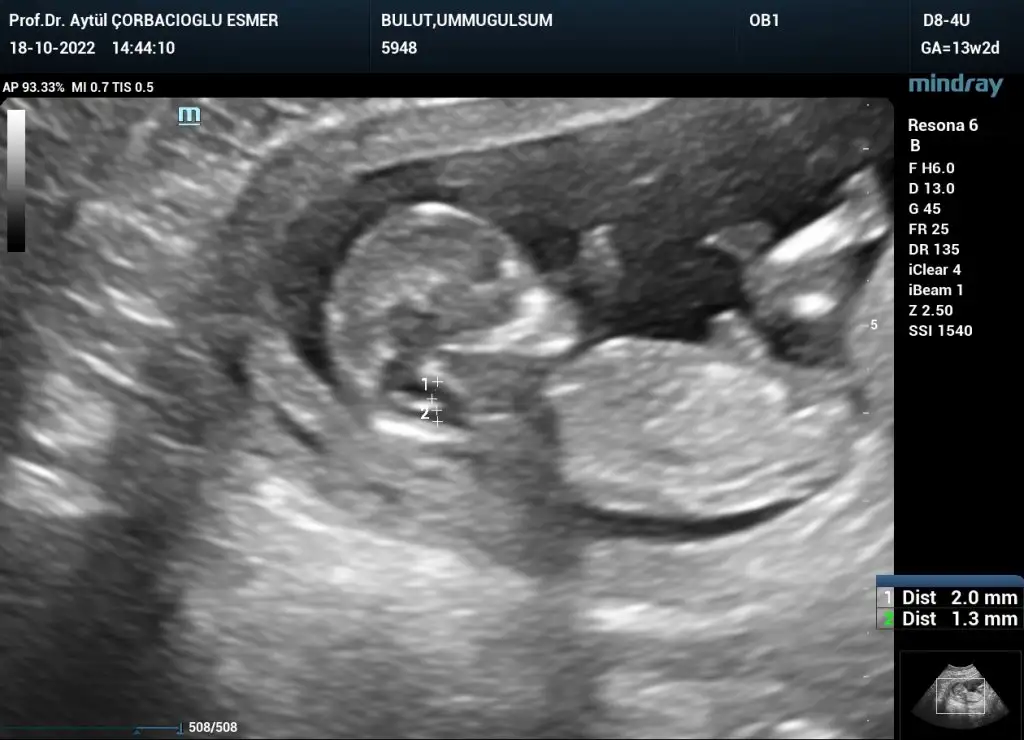

Kızlar selam kontrolden çıktım her şey yolunda çok şükür 15+4 kısa kısa ben de bahsedilenlere ben de cevap vereyim;

Son olarak yakışıklı oğlumu bırakıyorum buraya teyzeleri, hepinizi öpücükler🤍